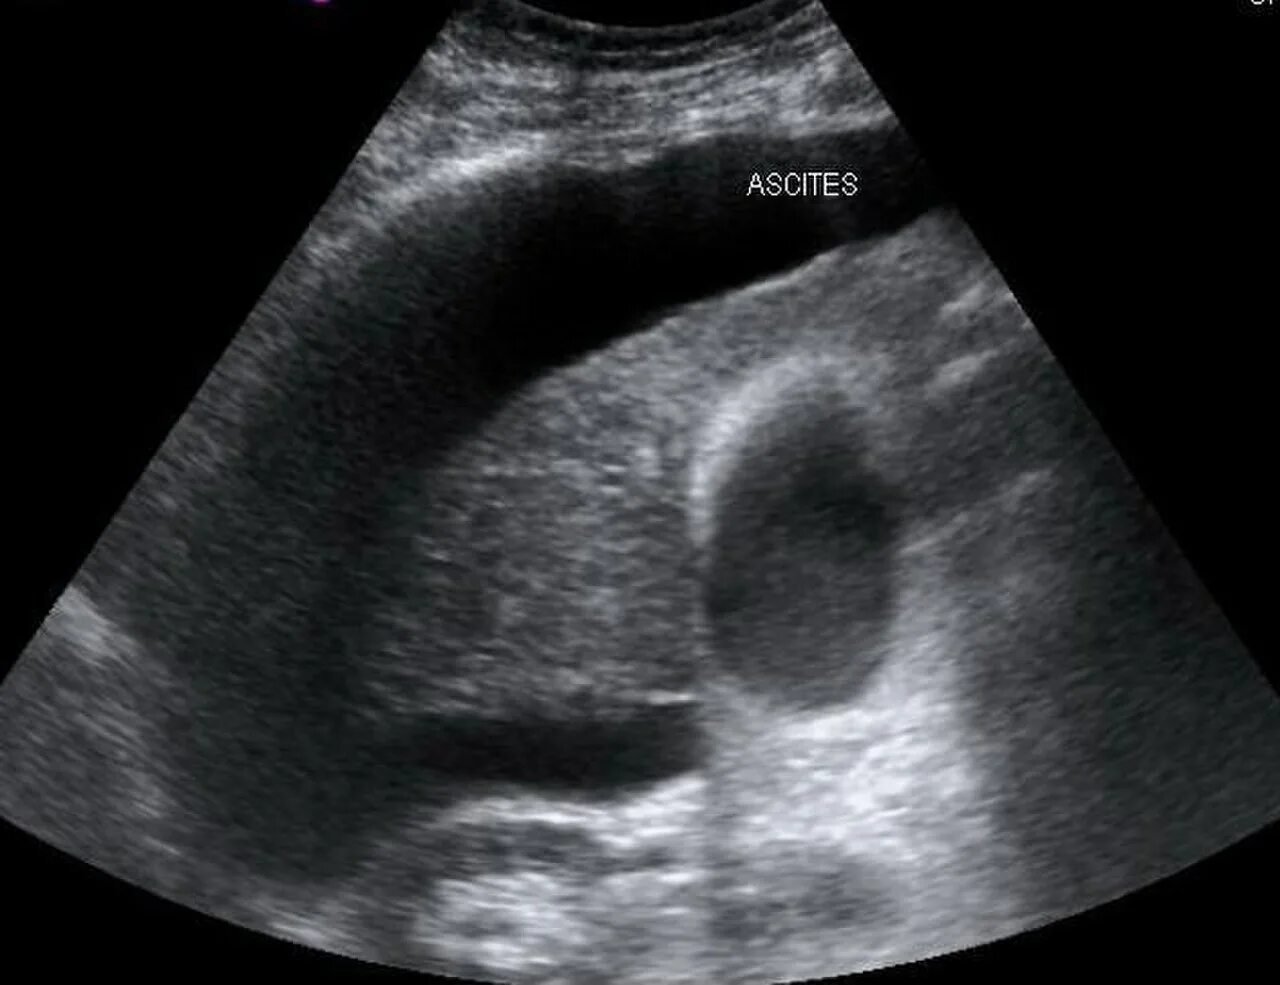

Асцит в малом тазу